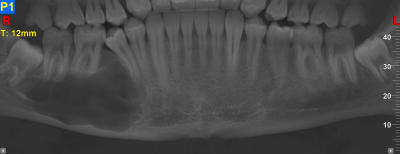

J'en ai déjà eu 3 comme ça, originaires de pays de l'est voir de l’extrême-est.

Un père pour un trou de 48 à 36 et son fils autour d'une 43 incluse. (origine génétique ?)

Et un autre au niveau latéral doit.

Idem adressé au CHU le plus proche.

Bon je sais , ça fait un peu le concours de celui qui à le plus gros ... kyste !!

Qui dit mieux ?